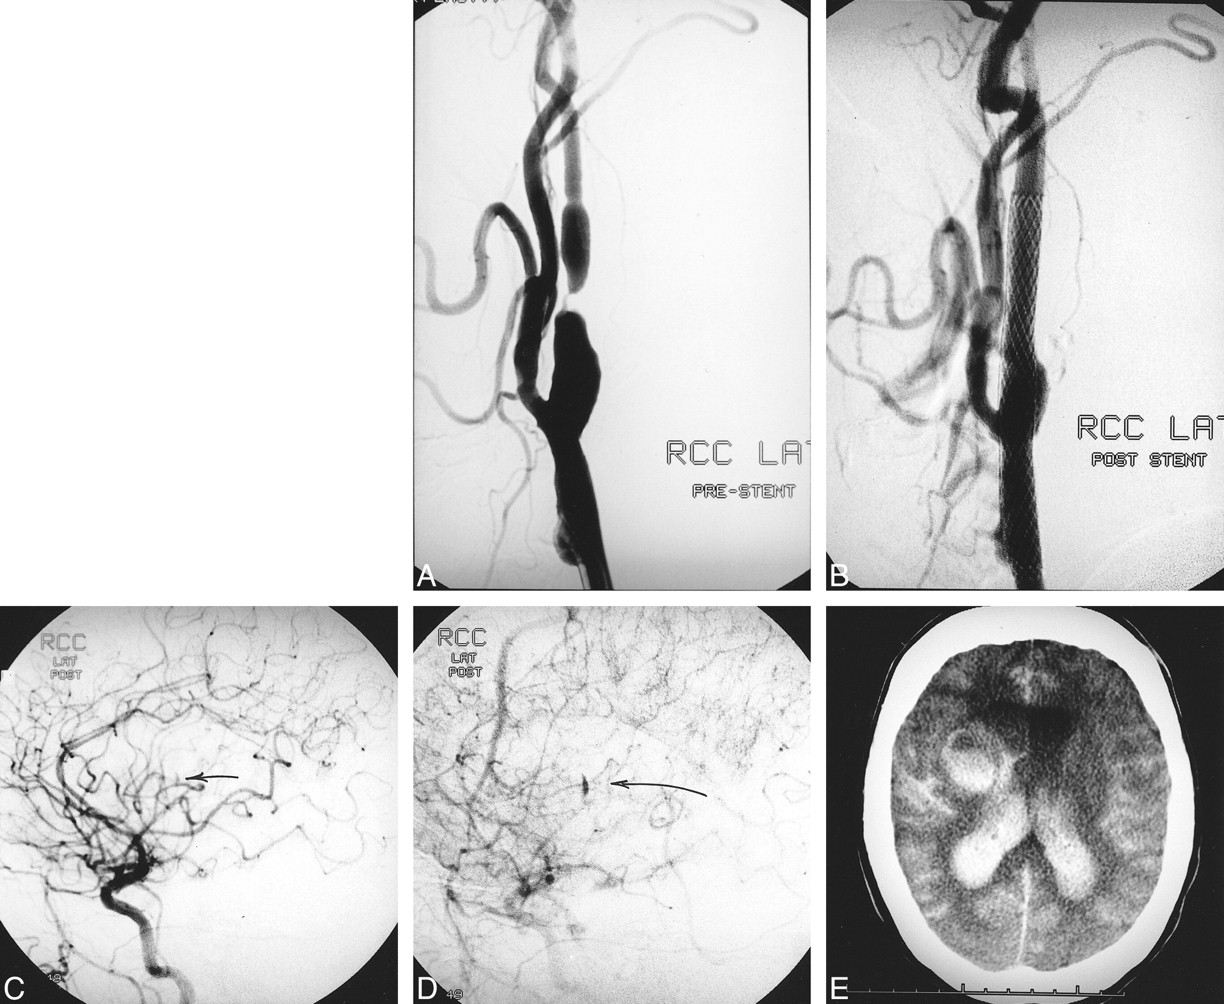

Patient 3. A, Ninety-nine percent right internal carotid artery stenosis. A left external carotid stent is also visualized. The left internal carotid artery is occluded.

B, Postprocedural angiogram with no significant residual stenosis post angioplasty and stenting.

C, CT of head 6 days postoperatively reveals an acute frontal hematoma with associated subarachnoid hemorrhage. The patient was clinically well until he experienced a generalized seizure approximately 2 hours prior to the CT scan.

D, Two-week follow-up reveals marked resolution of hemorrhage.

Patient 4. A, Ninety-five percent right internal carotid artery stenosis.

B, Post angioplasty and stenting with no significant residual stenosis.

C and D, Angiogram immediately post stenting demonstrates extravasation from a lenticulostriate artery (arrow). At no time during the procedure did a catheter or guidewire enter into the intracranial circulation.

E, CT of head postoperatively shows a right basal ganglia, intraventricular, and subarachnoid hemorrhage as well as hydrocephalus.